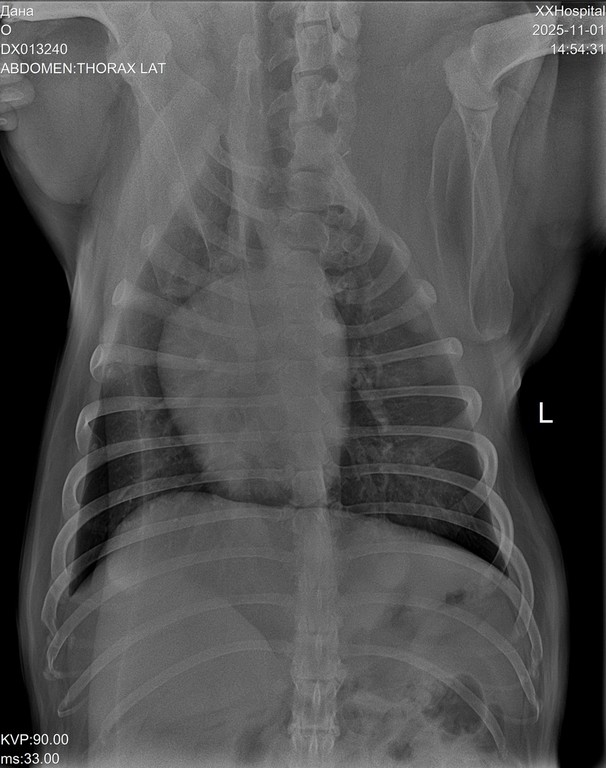

Дама в возрасте, лет 8-9. Вся в новообразованиях. В том числе раздут один сосок, откуда выделяется жидкость.